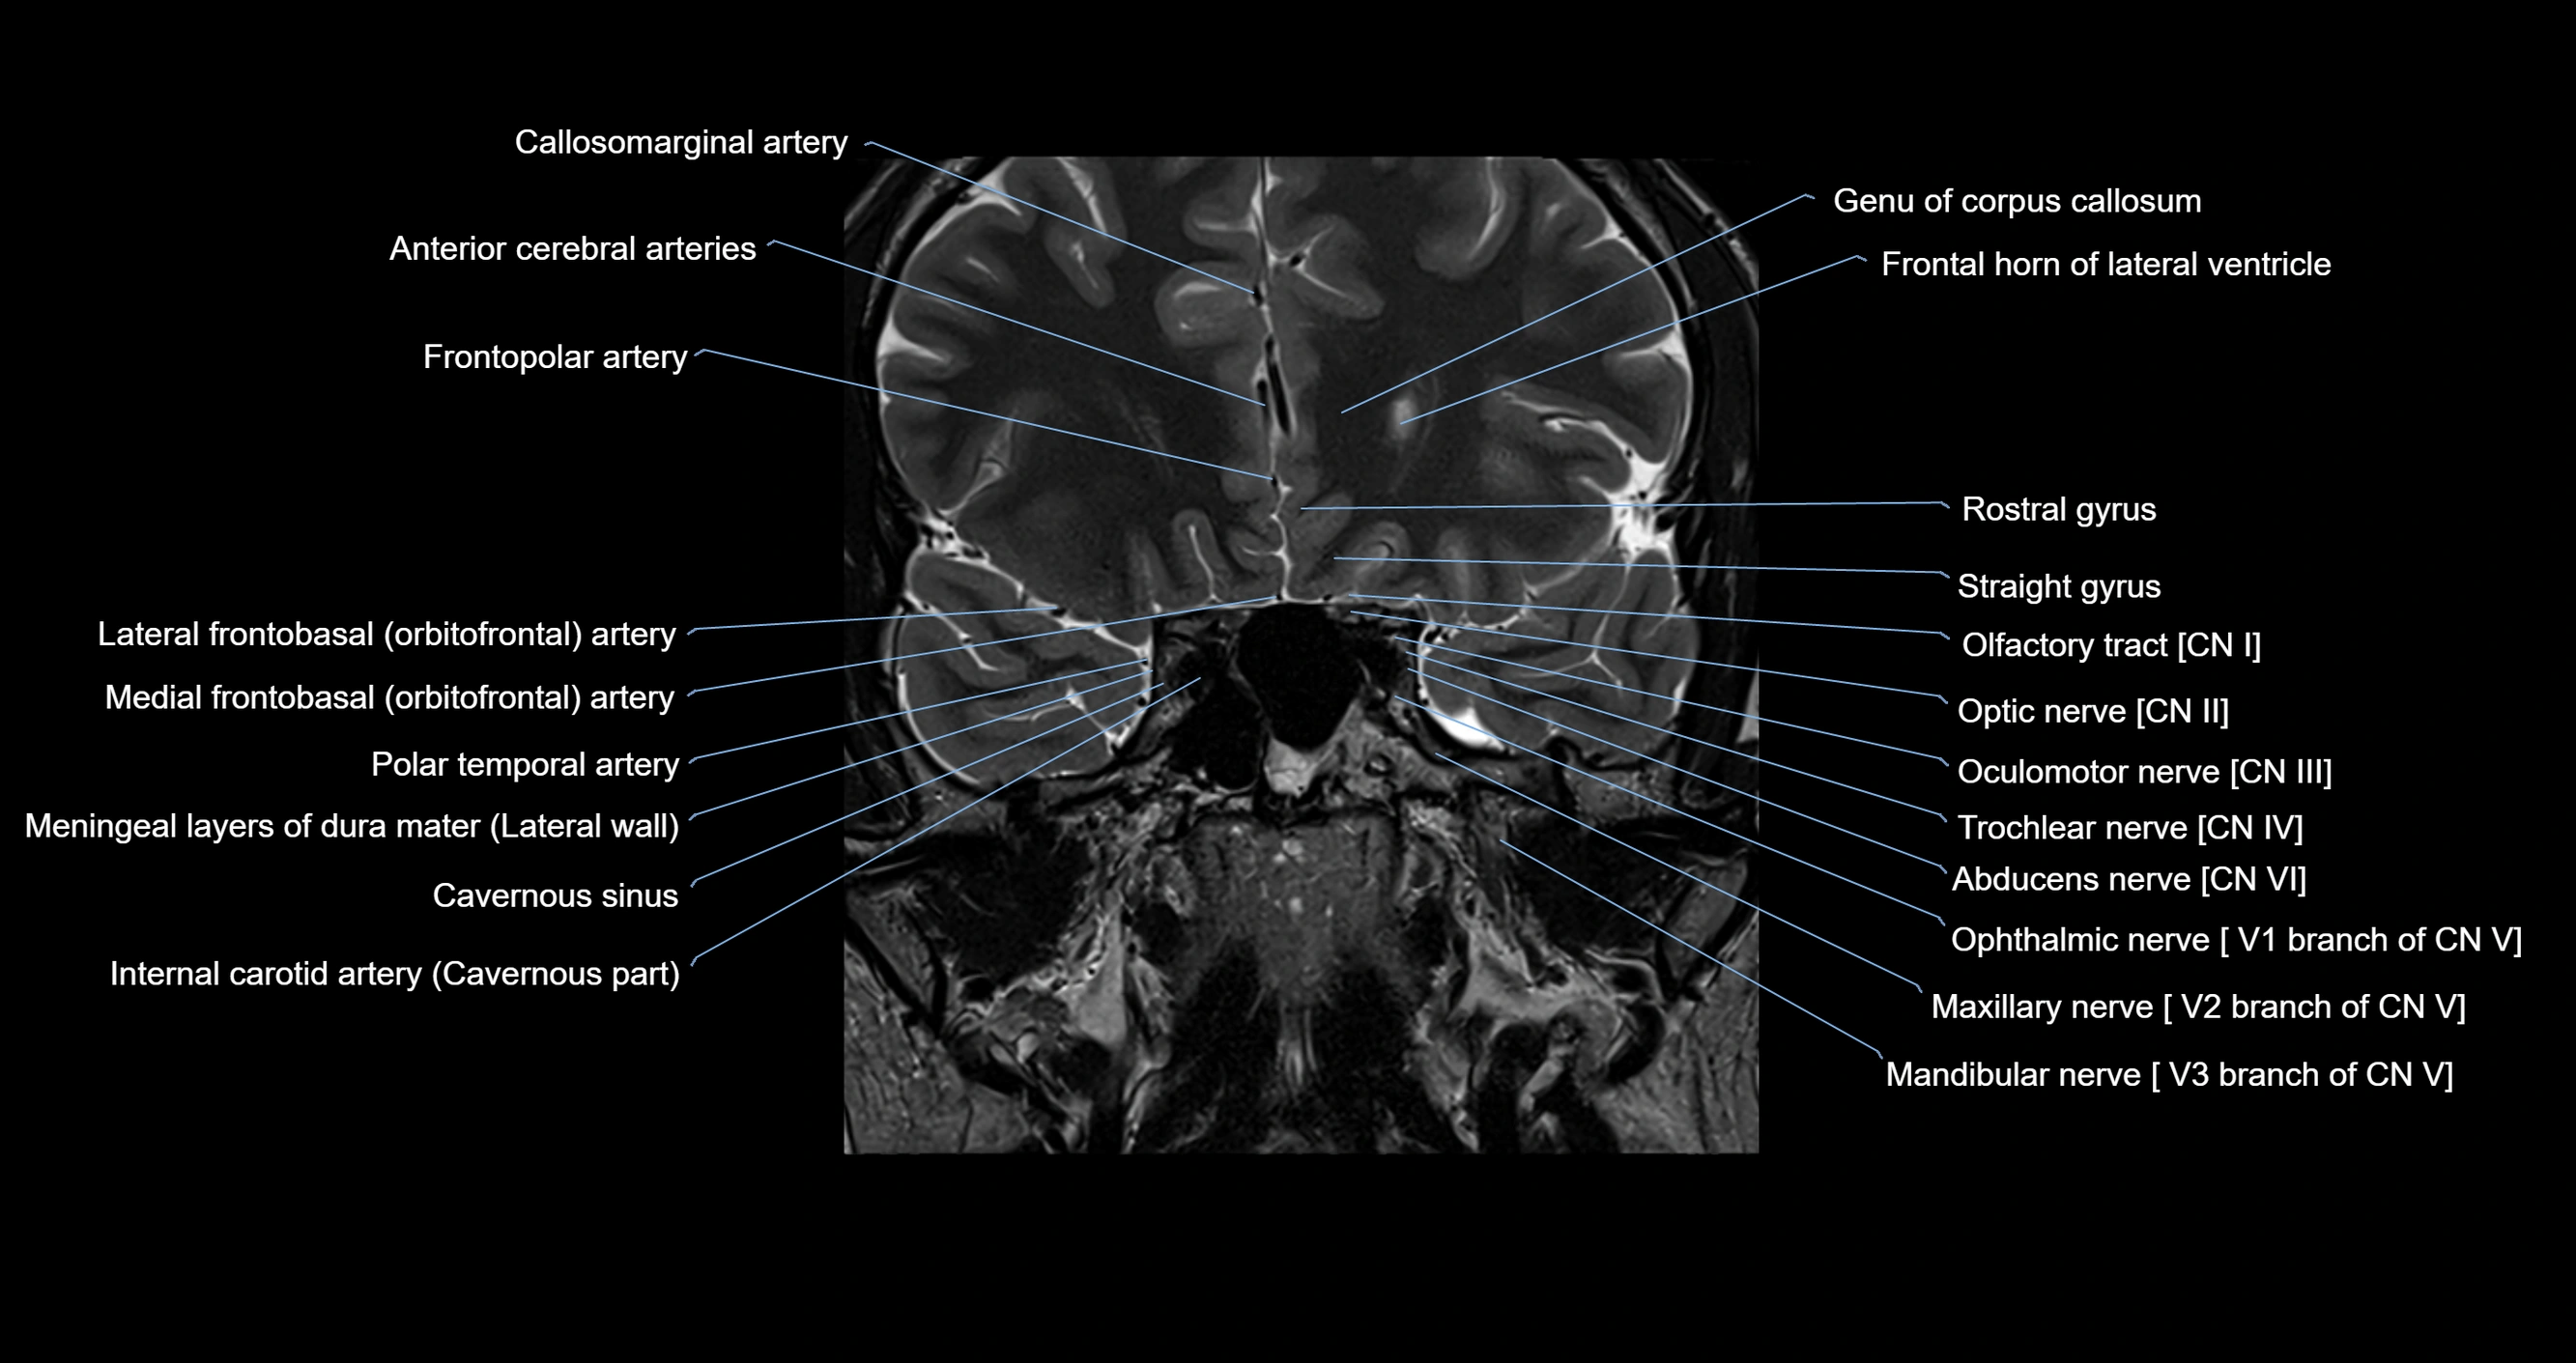

MRI images